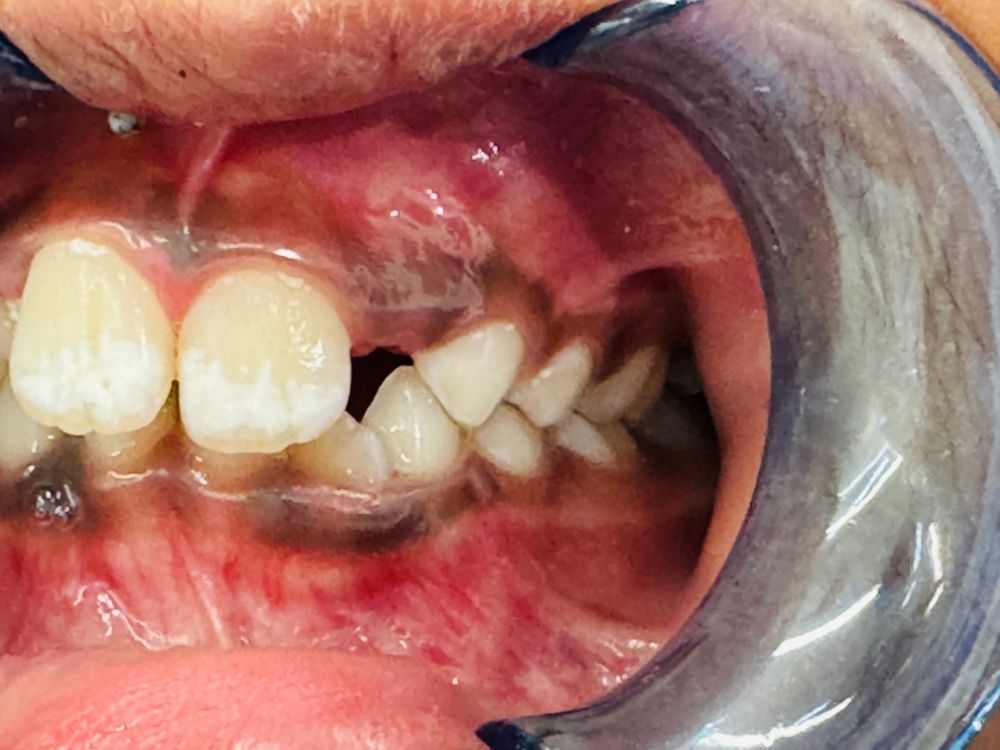

Emergencies We understand that dental emergencies can happen at any time. Whether it’s a chipped, broken, or painful tooth, our pediatric dental team is ready to provide fast, compassionate care to get your child smiling again.

As your child’s mouth grows, our team monitors their dental development closely. If a baby tooth is lost too early, a space maintainer helps preserve room for the permanent tooth to erupt correctly. In cases where a tooth needs extra protection, we may recommend stainless steel crowns to restore its function and durability — keeping your child’s smile healthy and strong.